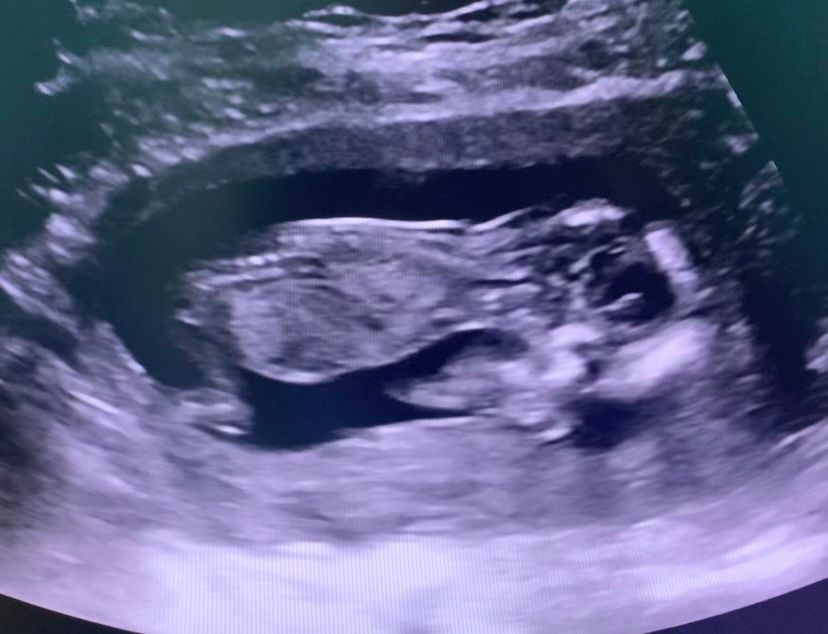

Эва, еще может быть узистка не айс поэтому не видит) не знаю почему но на последнем фото мне кажется я отчетливо вижу и носик и носовую кость

Солнце, вот и я кажется все вижу,может конечно потому,что хочу но уже хз,возможно она долго меня крутила и малыш говорит как-то неудобно лежит

У вас есть носовая косточка, я ее вижу. Уверена, у вас все хорошо

Family, 🙏вот и мне кажется я ее вижу,спасибо ❤️